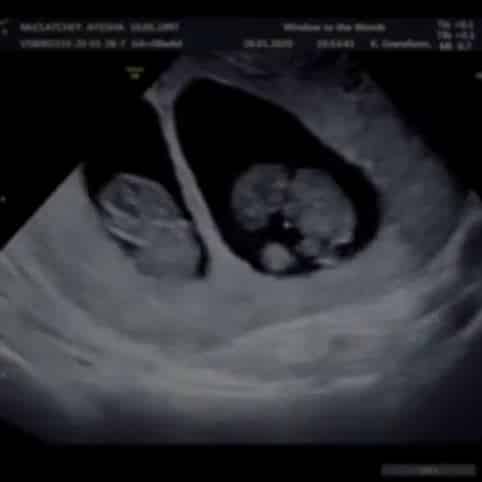

Last Tuesday marked a year ago since our first scan, the first time we ever saw our babies! We waited anxiously, my sickness heightened, we had hoped and prayed to see a healthy heartbeat.

I was drawn to a collage on the wall of then and now pictures. It was filled with scan photos and pictures a year on of babies who had safely entered the world. One picture clocked my attention, the couple had twins. I mentioned it to Dan and said to him to look, they had chosen 1 of our favourite baby names which was quite uncommon so it just made me smile. His response still makes me laugh to this day, he laughed and said, twins though babe, think that would be my worst nightmare. Well darling, your nightmare was quickly upon us.